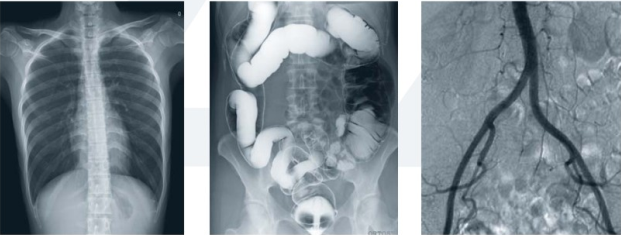

胃腸造影離不開(kāi)現(xiàn)代化的數(shù)字化胃腸顯影方式(一類(lèi)運(yùn)用常規(guī)胃腸機(jī)達(dá)到檢查目的;另一類(lèi)則運(yùn)用新推出的動(dòng)態(tài)DR達(dá)到檢查目的),它是一種能通過(guò)造影診斷用來(lái)檢查胃腸道疾病的X線(xiàn)檢查設(shè)備,是檢查各種潰瘍、腫瘤及異物等疾病的主要檢查方法之一。

隨著動(dòng)態(tài)DR的這股旋風(fēng)的盛起,部分胃腸機(jī)廠(chǎng)家也開(kāi)始大勢(shì)宣傳其胃腸設(shè)備同樣具備動(dòng)態(tài)功能。不過(guò)從市場(chǎng)的綜合反饋來(lái)看,雖然胃腸機(jī)在影像診斷上相比以前的醫(yī)療設(shè)備都有了較大的進(jìn)步,但和真正意義上的動(dòng)態(tài)DR依舊有一定的差距。

為什么目前市場(chǎng)上有很多客戶(hù)意愿選擇動(dòng)態(tài)DR這么一款多功能的產(chǎn)品作為替代胃腸機(jī)的一類(lèi)放射設(shè)備頭一個(gè)選擇,有哪些優(yōu)勢(shì)呢?常規(guī)胃腸機(jī)和動(dòng)態(tài)DR對(duì)比優(yōu)劣勢(shì)如下:

動(dòng)態(tài)DR胃腸造影檢查和消化內(nèi)鏡相輔相成,在胃腸道疾病的診斷方面具有其他檢查方法無(wú)可比擬的優(yōu)勢(shì)。僅在考慮特異性、適用性、普遍性的胃腸檢查上不難發(fā)現(xiàn),動(dòng)態(tài)DR胃腸造影檢查略有優(yōu)勢(shì)。特別是疑難病例上,全面分析胃腸大概狀況,離不開(kāi)造影的有效應(yīng)用。

同時(shí), 動(dòng)態(tài)DR的應(yīng)用實(shí)現(xiàn)了狀態(tài)和功能同時(shí)記錄觀(guān)察,既可留下大量的資料,又拓寬了檢查范圍,對(duì)臨床工作者的使用慣性和操作都有不可替代的地位。